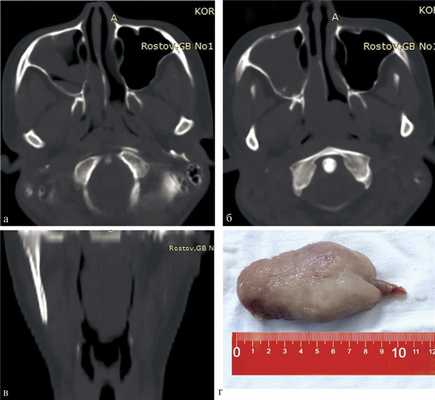

Пациентке была проведена спиральная компьютерная томография (СКТ) околоносовых пазух, которая позволила обнаружить АХП, исходящий из правой верхнечелюстной пазухи, спускающийся в гортаноглотку почти до уровня верхнего края надгортанника (рис. 1, а—в).

Рис. 1. СК-томограмма околоносовых пазух больной К. а, б — аксиальная проекция: определяется АХП, исходящий из правой верхнечелюстной пазухи и занимающий всю носоглотку; в — коронарная проекция: полип спускается в гортаноглотку до уровня края надгортанника; г — удаленный полип.

Удаление АХП было произведено под контролем эндоскопа под местной анестезией, поскольку интубация оказалась невозможной из-за дистальной части полипа, занимавшей гортаноглотку почти полностью. Сначала полип захватили зажимом через рот, затем его ножку пересекли на уровне выхода через добавочное соустье в задней фонтанелле, после чего полип был извлечен через рот (см. рис. 1, г). При ревизии пазухи через расширенное соустье была удалена оставшаяся часть полипа.

Данное наблюдение представляет интерес в связи с гигантскими размерами полипа, вызвавшего двустороннюю назальную обструкцию и нарушение дыхания в положении лежа на спине.